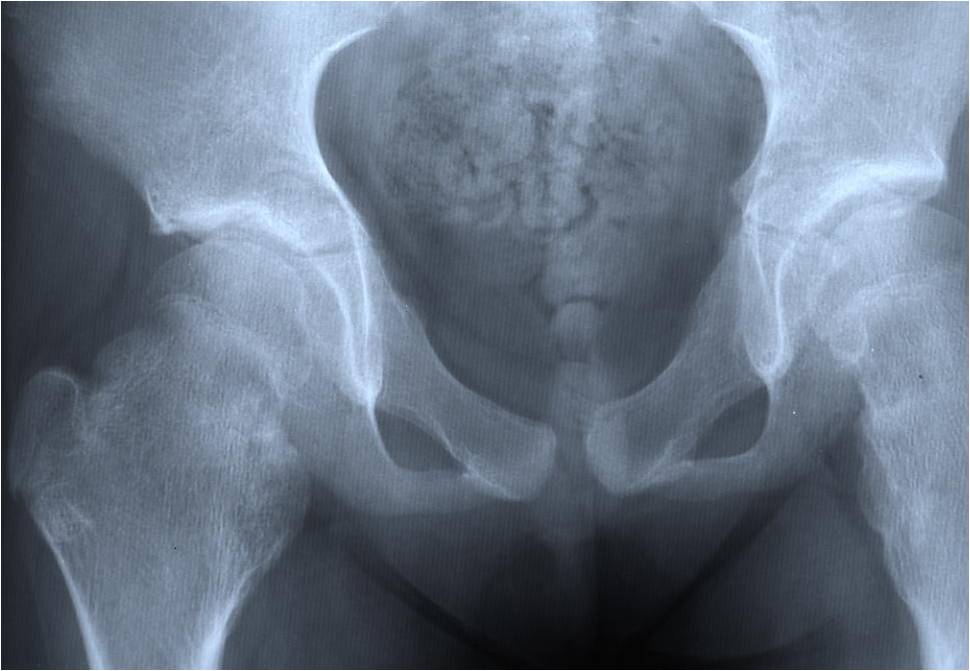

Plain X-ray: Secondary Chondrosarcoma of Proximal Femur

- Most common sites to undergo malignant change

- Scapula, pelvis, ribs, proximal femur

Osteochondroma Vs. Secondary Chondrosarcoma

The cartilaginous cap deserves the most attention when differentiating a benign osteochondroma from a secondary chondrosarcoma that arose from a pre-existing osteochondroma

Malignant transformation is suggested by:

- Cartilaginous cap thickness greater than 2cm

- Cortical destruction

- Backgrowth of the cartilaginous cap into the stalk or medullary canal

- Lysis of calcifications in cap